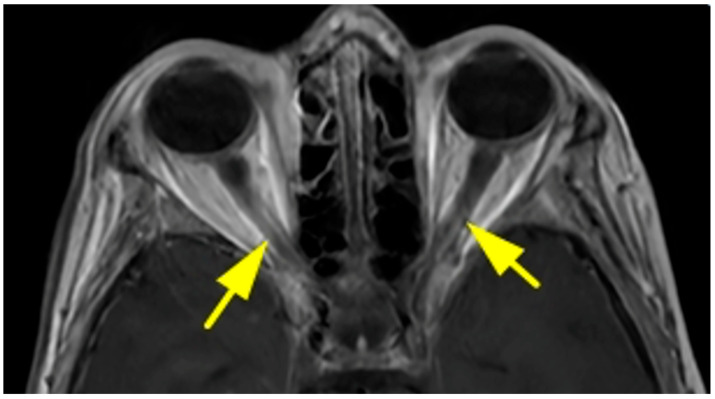

Background/Objectives: We aimed to evaluate the demographic characteristics, clinical findings, and survival outcomes of patients diagnosed with orbital metastasis, considering primary tumor type, age, and gender variables. Methods: In this observational study, demographic data, tumor localization, histopathological diagnoses, and survival times of 83 patients followed for secondary orbital metastasis at Çukurova University Ophthalmology Department between 2003 and 2023 were retrospectively reviewed. Subgroup analyses were performed according to age (<18 and ≥19), gender, and primary tumor groups. Results: The study included 83 patients (51 (61.4%) females and 32 (38.6%) males). The mean age at diagnosis was found to be 40.8 ± 24.6 years. A total of 24.1% of the cases were in the pediatric age group (mean age 5.9 years), and the most common tumor metastasizing to the orbit in this group was neuroblastoma (80%). In adult patients, the two most frequent tumors metastasizing to the orbit were breast cancer (33.3%) and lung cancer (14.3%). The most common clinical findings were proptosis (32.5%) and blurred vision (26.2%). Orbital metastases were observed more frequently in females than in males (61.4% vs. 38.6%). This ratio was similar in the pediatric age group (65.0% vs. 35.0%). The mean survival time after metastasis was calculated as 316.7 ± 68.6 days. Female patients had a significantly longer survival time after metastasis compared to males (mean 400.4 vs. 165.4 days; p = 0.037). The median survival after metastasis was 86 days for patients with breast cancer and 204 days for patients with neuroblastoma. Conclusions: The most common source of orbital metastases in females is breast cancer, while neuroblastoma is prominent in pediatric patients. Despite all available treatment options, the prognosis after orbital metastasis is poor; this highlights the importance of early diagnosis and a multidisciplinary approach.